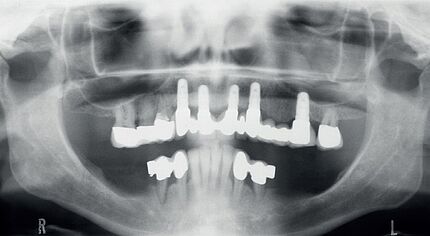

Ein 34-jähriger Patient hatte die häusliche Mundhygiene ohne erkennbare Gründe fast vollkommen eingestellt. Die daraus resultierende desolate orale Gesamtsituation war mit seinem äußeren Erscheinungsbild und seinem sozialen Status nicht vereinbar. Aufgrund dieser Widersprüche erfolgte eine intensive Abwägung der Therapieoptionen.

Zeitschrift: ZM – Zahnärztliche Mitteilungen

Ausgabe: 21/2019, Seiten 46 – 50

Freigabe zur Veröffentlichung erteilt durch den Deutschen Ärzteverlag

Autoren: PD Dr. Michael Korsch, M.A., Dr. Abdel-Karim Mamar